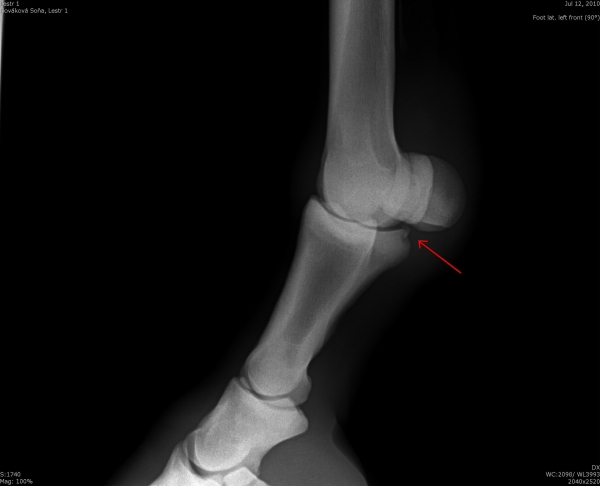

Fragment na spěnkové kosti